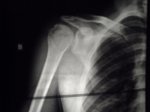

1ª FOTO DESCOLOCADO....2ª YA REDUCIDO